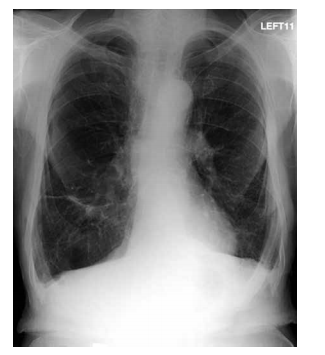

de oxigênio de 85%; ausculta pulmonar: expiração prolongada e discretos sibilos difusos. Radiografia de tórax

é mostrada a seguir.